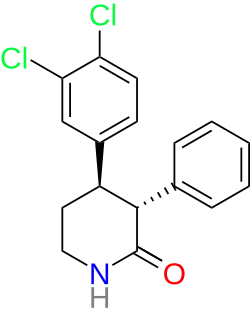

(+)-CPCA ("nocaine")[190] is the 3R,4S piperidine stereoisomer of (phenyltropane based) RTI-31.[191] It is non addictive, although this might be due to it being a NDRI, not a SNDRI. The β-naphthyl analog of "Nocaine"[112] is a SNDRI though in the case of both the SS and RR enantiomers. Consider the piperidine analogs of brasofensine[79] and tesofensine.[192] These were prepared by NeuroSearch (In Denmark) by the chemists Peter Moldt (2002),[193] and Frank Wätjen (2004–2009).[194][195] There are four separate isomers to consider (SS, RR, S/R and R/S). This is because there are two chiral carbon sites of asymmetry (means 2 to the power of n isomers to consider where n is the number of chiral carbons). They are therefore a diastereo(iso)meric pair of racemers. With a racemic pair of diastereomers, there is still the question of syn (cis) or anti (trans). In the case of the phenyltropanes, although there are four chiral carbons, there are only eight possible isomers to consider. This is based on the fact that the compound is bicyclic and therefore does not adhere to the equation given above.